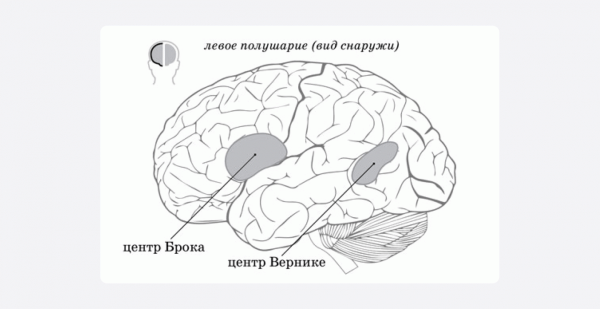

Первым, кто внес значительный вклад в изучение речи, стал Поль Брока — выдающийся французский хирург и антрополог. В 1865 году он опубликовал работу об открытии центра речи, который впоследствии и назвали центром Брока. После смерти двух пациентов с речевыми нарушениями (афазиями) ученый изучил их мозги и обнаружил поражения в одних и тех же областях левого полушария. А точнее — в нижней задней части третьей лобной извилины (оба пациента — правши).

Брока сделал вывод, что обнаруженный центр отвечает за моторную организацию речи. Если в этой области есть поражения, то возникает нарушение, которое позже назвали афазией Брока — то есть трудности с воспроизводством речи.

Чуть позже еще одно важное открытие сделал немецкий психоневропатолог Карл Вернике. Изучив мозг умершего пациента, который ранее перенес инсульт и имел серьезные проблемы с речью, он обнаружил поражение, локализованное в левом полушарии, в задней теменной и височной области. Вернике сделал вывод о том, что эта область участвует в понимании речи. Еще позже он обнаружил, что при повреждении волокон, которые соединяют поля Вернике и Брока, также возникает афазия.

Более того, метаанализ 2016 года, посвященный определению границ центров Брока и Вернике, показал, что в установке границ этих зон выявлены серьезные разночтения.